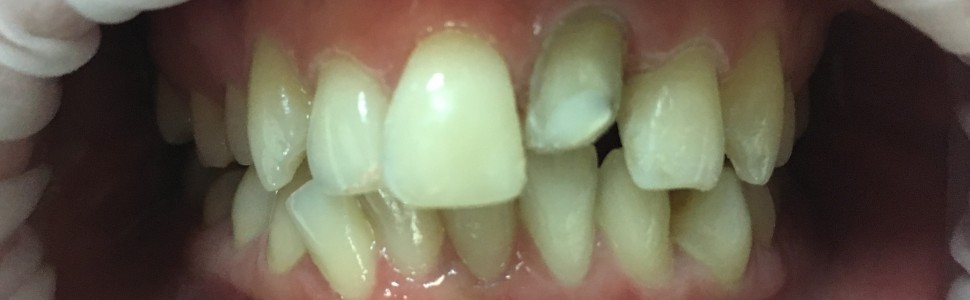

Odroczone zaopatrzenie protetyczne zęba po zwichnięciu całkowitym wraz z powikłaniami. Opis przypadku

Postponed avulsed tooth reconstruction and complications – case report

Urazy zębów są jednymi z najbardziej nieprzewidywalnych w skutkach sytuacjami w stomatologii. Nawet w pełni prawidłowe postępowanie podczas udzielania pierwszej pomocy pourazowej nie gwarantuje uniknięcia powikłań, które mogą być wczesne lub wystąpić dopiero po wielu latach. Z tego względu zęby po urazach należy oddawać regularnej kontroli. Każdą z form ich odbudowy trzeba traktować, jako potencjalnie tymczasową ze względu na możliwą konieczność reinterwencji w przyszłości.

Tooth injuries are one of the most unpredictable outcomes in dentistry. Even fully correct first aid procedures do not always allow to avoid complications that may appear immediately or even after many years. For this reason teeth after injuries should undergo periodic control. Each form of their reconstruction should be treated as potentially temporary due to the possible need for re‑intervention in the future.